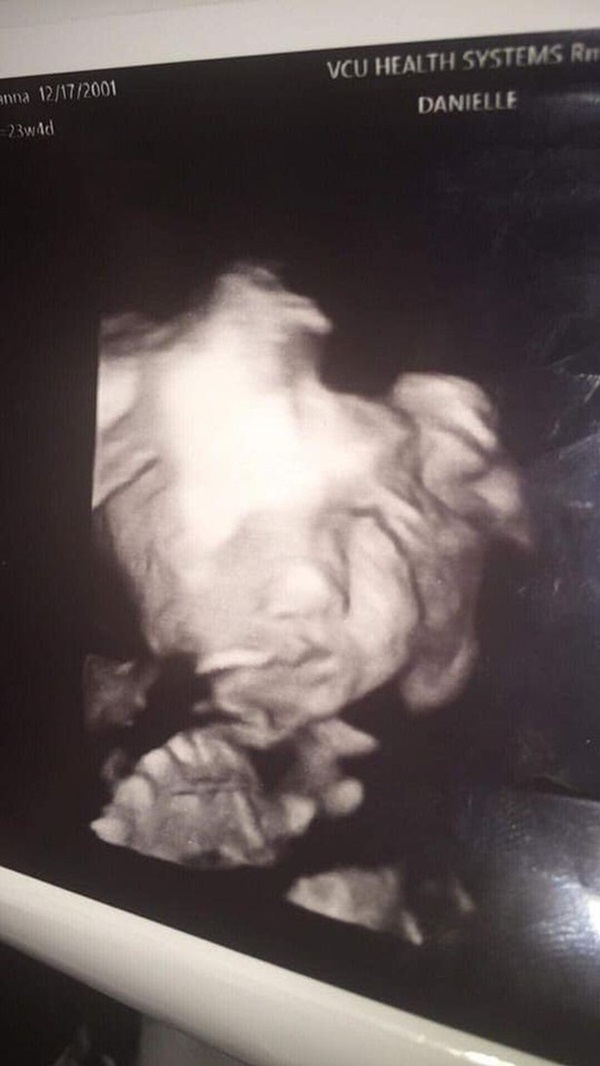

Trong lần siêu âm thai nhi 24 tuần tuổi mới đây, cô Iyanna Carrington, tới từ Richmond, bang Virginia, Mỹ không chỉ cảm thấy hồi hộp mà còn có chút sốc khi thấy mặt con mình.

Bà bầu này kể lại: "Trong lần siêu âm này, tôi sẽ biết giới tính của con. Lúc đầu họ chiếu mặt đứa bé thì bình thường, y tá cho biết đây là một bé gái. Sau đó họ chiếu lại mặt đứa bé một lần nữa thì có cảnh tượng này, con gái cứ nhìn thẳng về phía tôi như thế. Tôi nói 'nhìn bé như một bóng ma' ngay giữa phòng và bác sĩ đáp lại thản nhiên 'Ừ, chuyện này cũng bình thường thôi mà'.".

Khi siêu âm ai cũng muốn được thấy mặt con mình nhưng không phải với đôi mắt mở to, miệng hé cười như thế này cả. Dù có chút kì dị nhưng em bé của Iyanna phát triển khỏe mạnh và bình thường.

Một bức ảnh khác của bé con 24 tuần tuổi của nhà Iyanna Carrington.